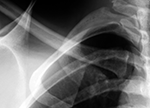

Which examinations may be considered in an individual case depends on the procedural situation and the legal basis. Typical components are the physical examination, the dental examination including orthopantomogram, the radiological assessment of the hand, and, in cases of advanced maturity and a corresponding question, supplementary findings at the clavicle. What is decisive is the ordered overall appraisal; an isolated single finding does not carry the conclusion. The evidential value therefore does not arise from a single image or a single maturity feature, but from the methodologically grounded combination of the permissible findings.